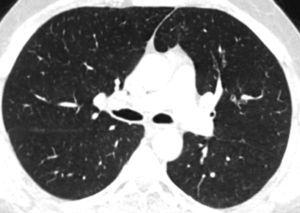

In our case, differential diagnosis was performed for primary (hematopoietic neoplasms with HE) and secondary HES, (helminth infections, allergic reactions, atopic diseases, drug reactions (allergic or toxic), Hodgkin disease, B- or T-cell lymphoma/leukemia, Langerhans cell histiocytosis, indolent systemic mastocytosis, solid tumors/malignancy, allergic bronchopulmonary aspergillosis, chronic inflammatory disorders, autoimmune diseases and lymphoid variant of HES), organ-restricted conditions accompanied by HE (eosinophilic gastrointestinal disorders, eosinophilic pneumonia, dermatologic diseases, etc.) and specific syndromes accompanied by HE (Gleich syndrome, Churg-Strauss syndrome, eosinophilia myalgia syndrome, Hyper-IgE syndrome).1, 2, 3, 4, 5, 6 The patient was diagnosed with idiopatic HES after exclusion of all primary and secondary causes and exclusion of other conditions and syndromes. The patient was started on imatinib mesylate therapy with 400 mg/day because he did not respond to corticosteroids (CS) and hydroxyurea therapy. The treatment was reduced to a 100 mg in the third month of treatment due to normalization of eosinophil levels and disappearance of all complaints. The ground-glass nodules disappeared after 1 year of imatinib treatment (Figure 1b).

Figure 1b. Axial CT image at the same level as in Fig. 1a showing disappearance of ground-glass nodules.